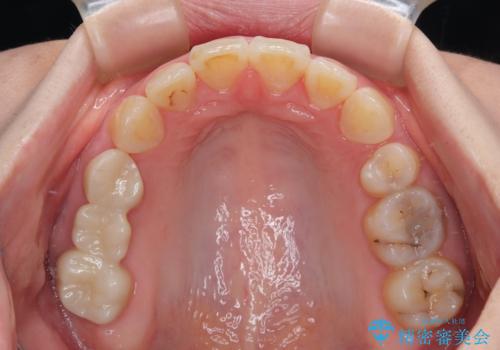

- 飛び出した上顎前歯を気にして来院された患者様です。

下顎は左右2番目の歯が2本欠損しており、上下前歯の前後的な位置は著しくずれている状態でした。

骨格的にも上顎骨が前突傾向にあり、極端な過蓋咬合になっていました。

強い咬合力に抵抗するように歯を動かす必要があるにもかかわらず、上顎第一大臼歯が1本欠損しているため、治療は困難を極めることが予想されました。